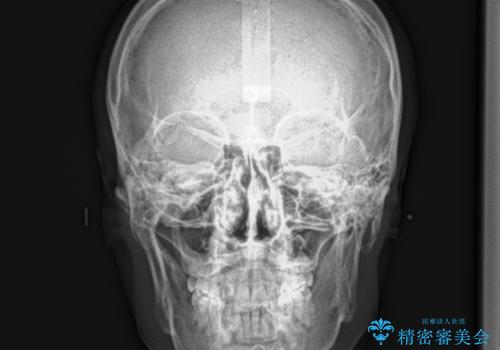

- 30代男性

- 以前、上下左右4本抜いてワイヤー矯正をしていた方で、後戻りで下の前歯のガタガタを気にして来院されました。

マウスピース矯正にて、下の歯はIPR(歯と歯の間を削る)を入れることでガタガタの改善、咬み合わせの深さも改善をはかる治療計画をたてました。